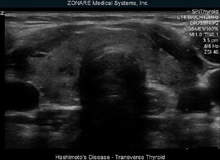

Such is the technology’s popularity that manufacturer Zonare Medical Systems has become one of the fastest-growing medical companies in the US.

In the UK, the system is taking longer to take off but there are still about 100 installed, according to ultrasound manufacturer Zonare managing director David Thomas.

“We came up with a completely different way of acquiring the data,” Thomas says.

“Because you still have the raw data from the original scan, you can run different processes on it to look at what has been scanned in different ways. It gives better contrast and a more accurate representation of what has been scanned.”